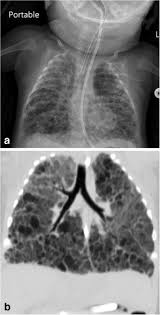

Fig 10 2 A Former 32 Week Gestation Now Diseases Of The Chest Breast Heart And Vessels 2019 2022 Ncbi Bookshelf

Pelvic inflammatory disease chronic. However prior to the description in 1967 of bronchopulmonary dysplasia BPD following ventilator therapy for respiratory distress syndrome Wilson-Mikity syndrome WMS had been described in very preterm infants on minimal oxygen supplementation. Bronchopulmonary dysplasia is also known as. Most babies who now develop chronic lung disease have a birth weight below 1000 g and have only mild early respiratory disease requiring minimal ventilation and low concentrations of inspired oxygen. Its incidence varies from 10 to 60 in different regions of Chile. Chronic lung disease is defined as oxygen dependency at 36 weeks corrected gestational age. Diuretics and corticosteroids are effective in achieving short-term improvement in the status of ventilator dependent babies. Advances in both perinatal and neonatal care over the past two decades have improved the survival of very preterm births but morbidity is significant among the survivors1 2 3 Chronic lung disease of prematurity CLD often also called bronchopulmonary dysplasia BPD is one of the most common sequelae in preterm births. Bronchopulmonary dysplasia BPD is a chronic lung disease most commonly seen in premature infants who required mechanical ventilation and oxygen therapy for acute respiratory distress but can also occur in neonates that had a less severe respiratory course 13.

Most babies who now develop chronic lung disease have a birth weight below 1000 g and have only mild early respiratory disease requiring minimal ventilation and low concentrations of inspired oxygen. Day-to-day care is mostly directed towards improving symptoms with many common interventions. Bronchopulmonary dysplasia is a serious complication of prematurity resulting from poor lung growth and lung injury. However prior to the description in 1967 of bronchopulmonary dysplasia BPD following ventilator therapy for respiratory distress syndrome WilsonMikity syndrome WMS had been described in very preterm infants on minimal oxygen. Chronic lung disease is defined as oxygen dependency at 36 weeks corrected gestational age. Dysplasia means abnormal changes in the. Chronic Neonatal Lung Disease Bronchopulmonary dysplasia BPD first described in 1967 by Northway Defined as O 2 dependence at 28 days post birth Now termed old BPD Post-surfactant era new BPD arrest at the canalicular phase of lung development Definition changed in 1988 to O 2 dependence at 36 wks Incidence of BPD.